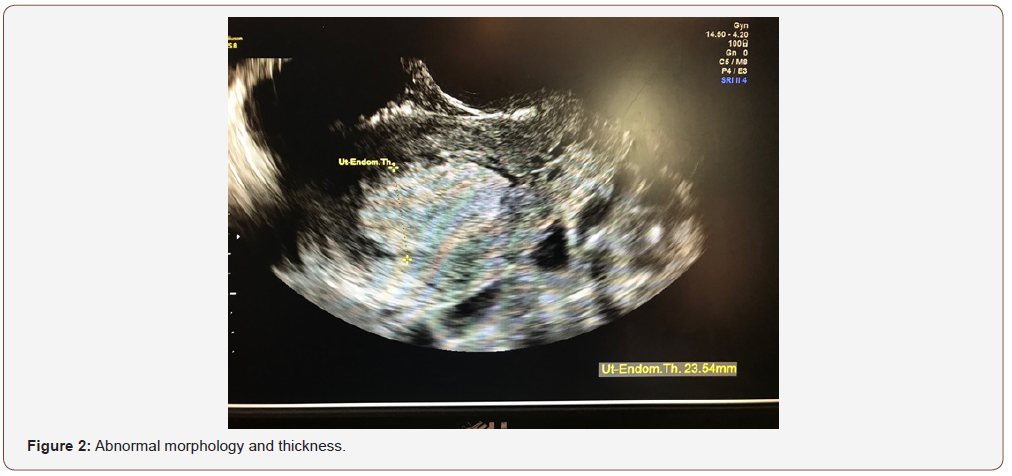

An evaluation of endometrial morphology included an assessment of endometrial echogenicity, the endometrial midline and the endometrial-myometrial junction. A ‘uniform’ endometrium included the three-layer pattern (Figure 1), as well as a homogenous hyperechogenic, hypoechogenic and is echogenic endometrium. The echogenicity is defined as ‘non-uniform’ if the endometrium appears heterogenous, asymmetrical or cystic (Figure 2). The endometrial midline was defined as ‘linear’ (Figure 3), if a straight hyperechogenic interface within the endometrium is visualized, as ‘non-linear’ if a waved hyperechogenic interface is seen, and as ‘irregular’ or as ‘not defined’ in the absence of a distinct interface (Figure 4). All studies were performed at the AIUM certified sonographic unit.